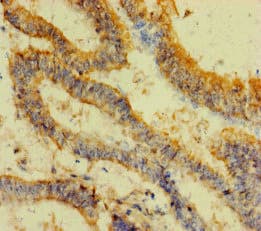

Rabbit Polyclonal RS30 antibody. Suitable for IHC-P, ICC/IF and reacts with Human samples. Immunogen corresponding to Recombinant Full Length Protein corresponding to Human FAU.

Applications ICC/IF, IHC-P